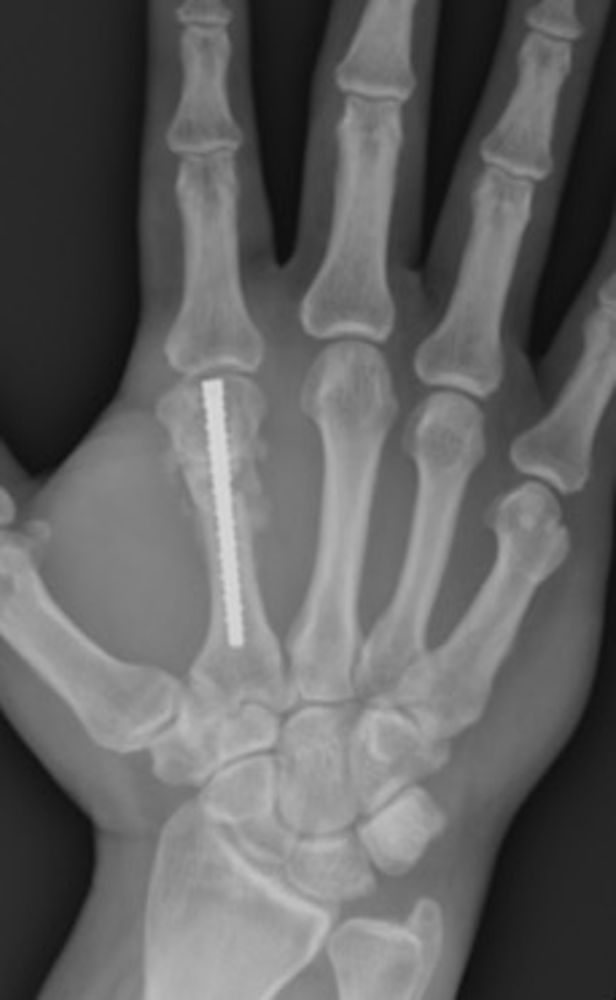

A 39-year-old male presented with a right index finger metacarpal neck malunion with a 30-degree extensor lag and an ulnar malrotation of the digit (Figures 1 and 2) after a fracture 8 months prior. The patient underwent right index finger metacarpal lengthening using iliac crest tricortical bone autograft, right index finger metacarpal joint dorsal and volar capsulectomy, as well as extensor tenolysis and A1 pulley release. A single-stage metacarpal lengthening was achieved with intercalary structural iliac bone graft and intramedullary screw. At 2-week follow-up, the patient had achieved length restoration that resolved extensor lag, reestablished cascade, and had appropriate rotation. At 3-month follow-up, the patient had achieved osseous union and maintained normal cascade of his hand with the ability to make a composite fist. In this article, we present this novel technique for single-stage metacarpal lengthening.

Figure 1. Preoperative posterior-anterior X-ray image of right hand with index finger metacarpal malunion.